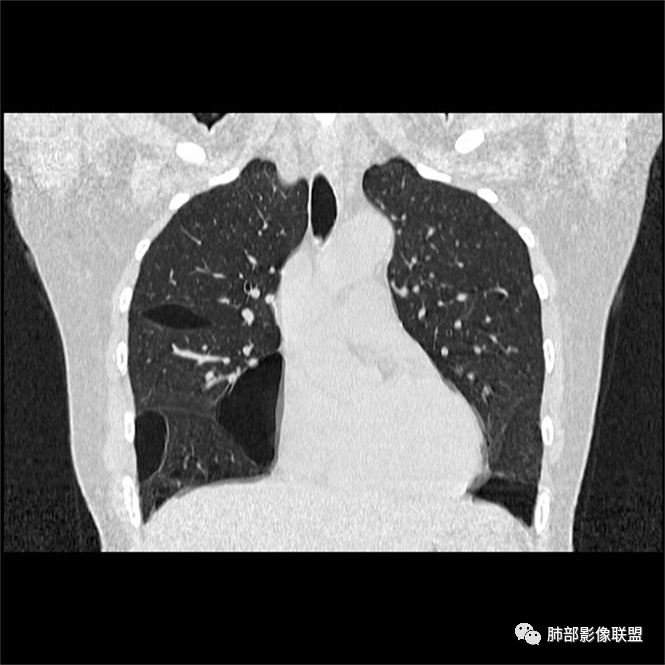

双肺弥漫囊腔,累及肋膈角,囊腔形态相对规则单一。

CT平扫示双肺弥漫分布大小不等囊状薄壁透光区,无内、中、外带分布差异,间质稍示增厚。拟LAM

女,46,活动性气喘1年。苯吸入史半年。胸部CT:两肺弥漫囊腔,上至肺尖,下至肋膈角,形态类似小囊腔。考虑:LAM,鉴别LIP,BHD,PLCH等。

双肺弥漫大小不一薄壁含气囊腔,囊间肺组织正常,正常肺背景,肺尖肺底受累;青年女性,气喘,支持LAM

CT表现:双肺弥漫大小不等的薄壁囊腔,囊壁<2mm,外形规则,血管影多位于囊腔周围,囊腔之间肺组织正常,随着疾病进展到晚期,囊腔变大、增多,不可胜数,囊腔可融合成较大的囊,与肺气肿相似,形成间质性肺纤维化。部分病例可出现结节影。